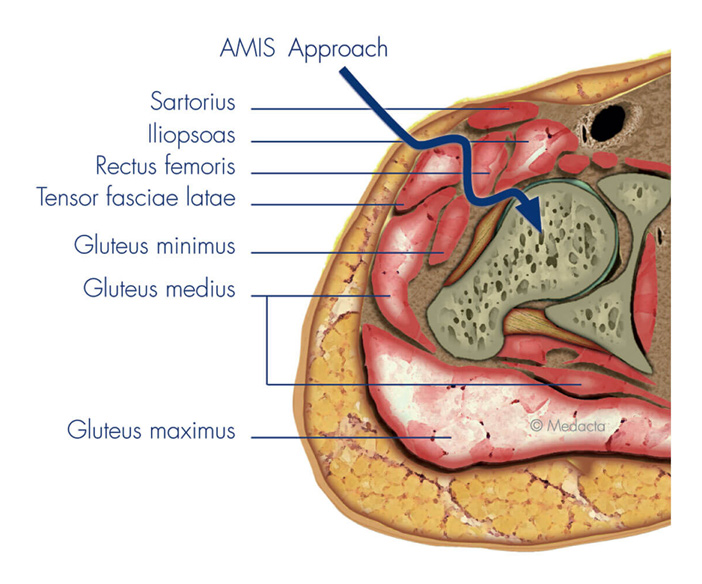

Choosing The Best Surgical Approach

The most suitable surgical approach depends on your anatomy, joint condition, past medical history, and recovery goals. Our surgeons at Melbourne Orthopaedic Clinic are highly experienced in multiple techniques and will guide you through the available options to ensure your surgery is both safe and effective.

Anterior Approach

The anterior approach, (AMIS/DAA) and more specifically the Medacta Direct Anterior Approach (MDAA), is a minimally invasive technique performed from the front of the hip with preservation of key muscle groups, including the hip abductors and external rotators. It supports faster recovery, reduced post-operative restrictions, and improves early mobility.

Both, an oblique, so called bikini incision or a longitudinal skin incision can be used for this approach.

Posterior Approach

The posterior approach is performed through an incision at the back of the hip provides excellent visibility of the acetabulum (hip socket) and the femur, making it useful in complex cases or revision surgeries. This technique involves detaching some of the short external rotators to access the joint, which are re-attached at the end of the procedure.

A smaller incision (mini-posterior approach), is often sufficient to perform this approach.

Your surgeon at Melbourne Orthopaedic Clinic will consider several factors when determining the most suitable approach for your total hip replacement. These include your hip anatomy, bone quality, any previous hip surgeries or scar tissue, as well as your mobility, muscle strength, and overall health. They will also take into account your recovery goals and evaluate potential risks.